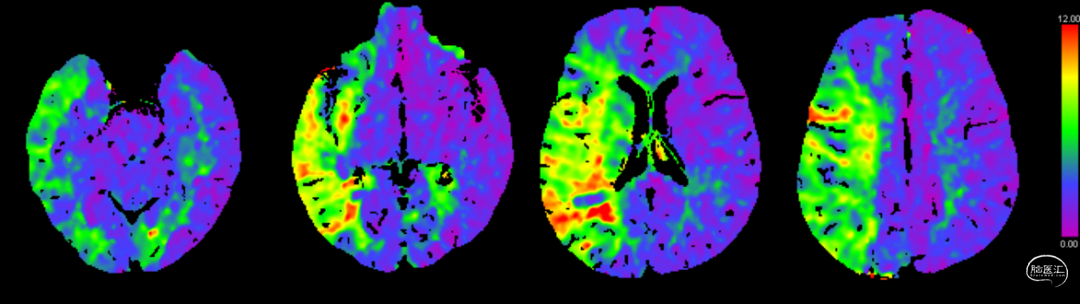

➢术前CTP

3.CTP提示:右侧大脑中动脉供血区域大片低灌注。

➢术后1周CTP